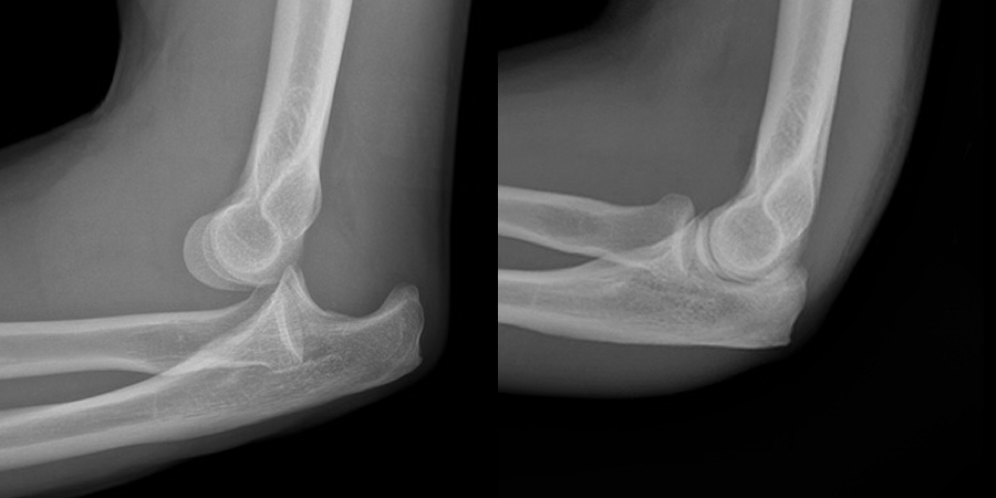

elbow fracture

FOOSH mechanism or direct hit

possible even incorrect reduction with elbow

symptoms: swelling, muscle spasm, pain, possible deformity, reduced ROM, compromised neurovascular

treatment: stabilize and ship

may need a sling or cast, or surgery

treatment will depend on cast vs. surgery